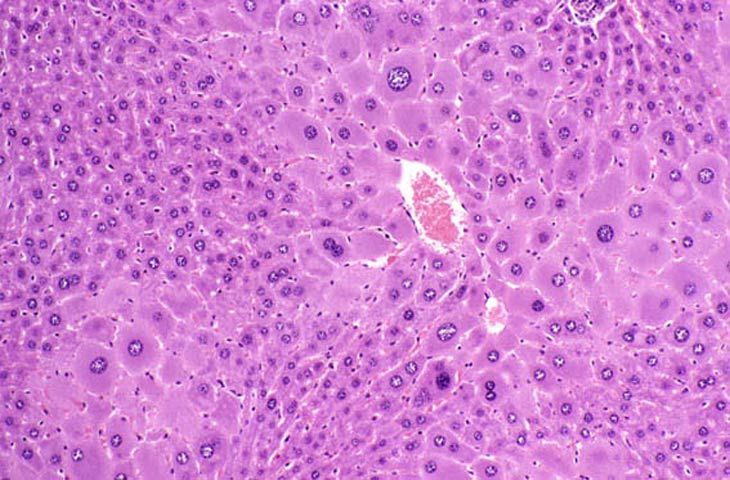

Extreme polyploidy consisting of cytomegalic hepatocytes with very large nuclei as well as cytomegalic hepatocytes with several diploid nuclei is seen in these images from a mouse treated with chlordane for 18 months.